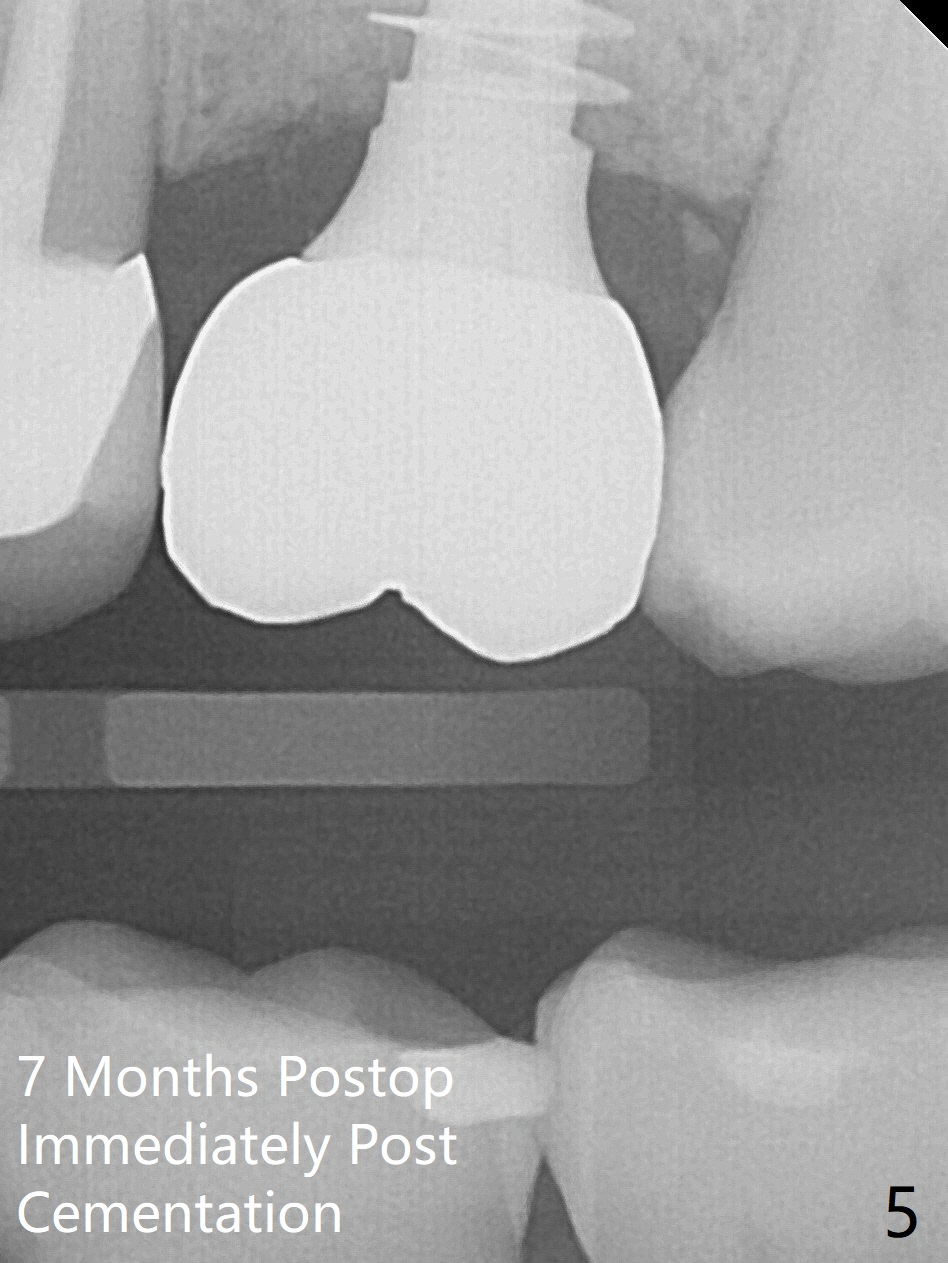

The ridge is wide at #14 11 months post socket preservation. Access and bone expansion (BEB) starts with Magic Split, followed by Magic Expanders 3.0, 3.8 and 4.3 mm from 8 to 9 mm for sinus lift. No bone is removed for osteotomy. Instead bone condensation occurs. After placement of a 4.5x11 mm dummy FC implant (Fig.1 with sinus lift (without bone graft)), a 5x9(2) mm Magicore (2 mm cuff) is placed with >55 Ncm with cuff margin at the gingival margin (Fig.2); a 5.5x3 mm solid abutment tries in. There is no occlusal clearance; trimming of the solid abutment will be needed. Later a healing screw is placed (Fig.3 *). There is no bone loss 5.5 months postop (Fig.4). A healing cap is placed without much tissue blanching. Instead a 5.5x3 mm solid abutment is placed; after height adjustment, impression is taken. A permanent crown is temporarily cemented 6 months postop (to rule out food impaction) and permanently re-cemented 7 months postop (Fig.5,6). CBCT taken 3-4 months post cementation shows that the implant threads are within the bone (Fig.7) and that the implant barely enters the sinus (Fig.8 *). That is significant since the patient has chronic sinusitis with thickened sinus membrane (Fig.9 *). The tooth #18 seems to have crazing line 10 months post cementation of the crown at #14 (overloading, Fig.10).